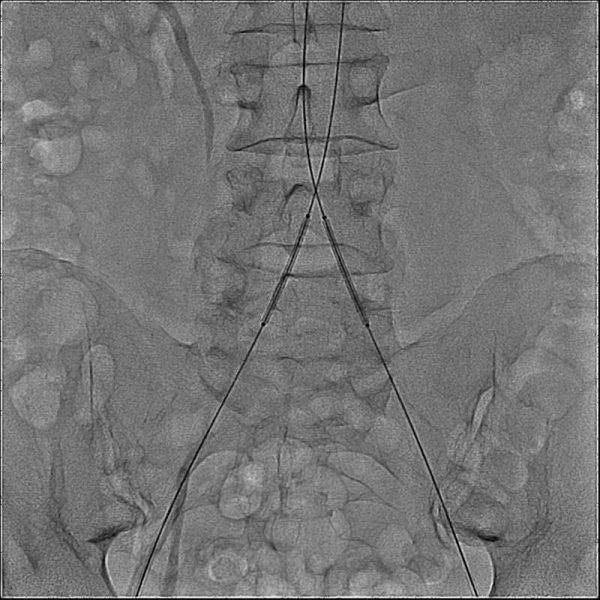

На первой иллюстрации – исходная артериограмма, где визуализуруется выраженное стенотическое атеросклеротическое поражение общих подвздошных артерий.